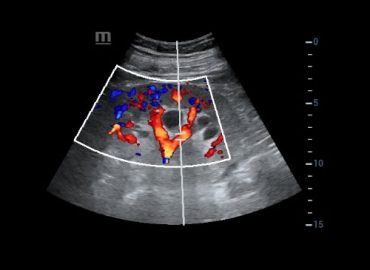

Paciente masculino de 47 años con antecedente de trasplante renal. Consulta a la guardia refiriendo cefalea de 48 hs de […]